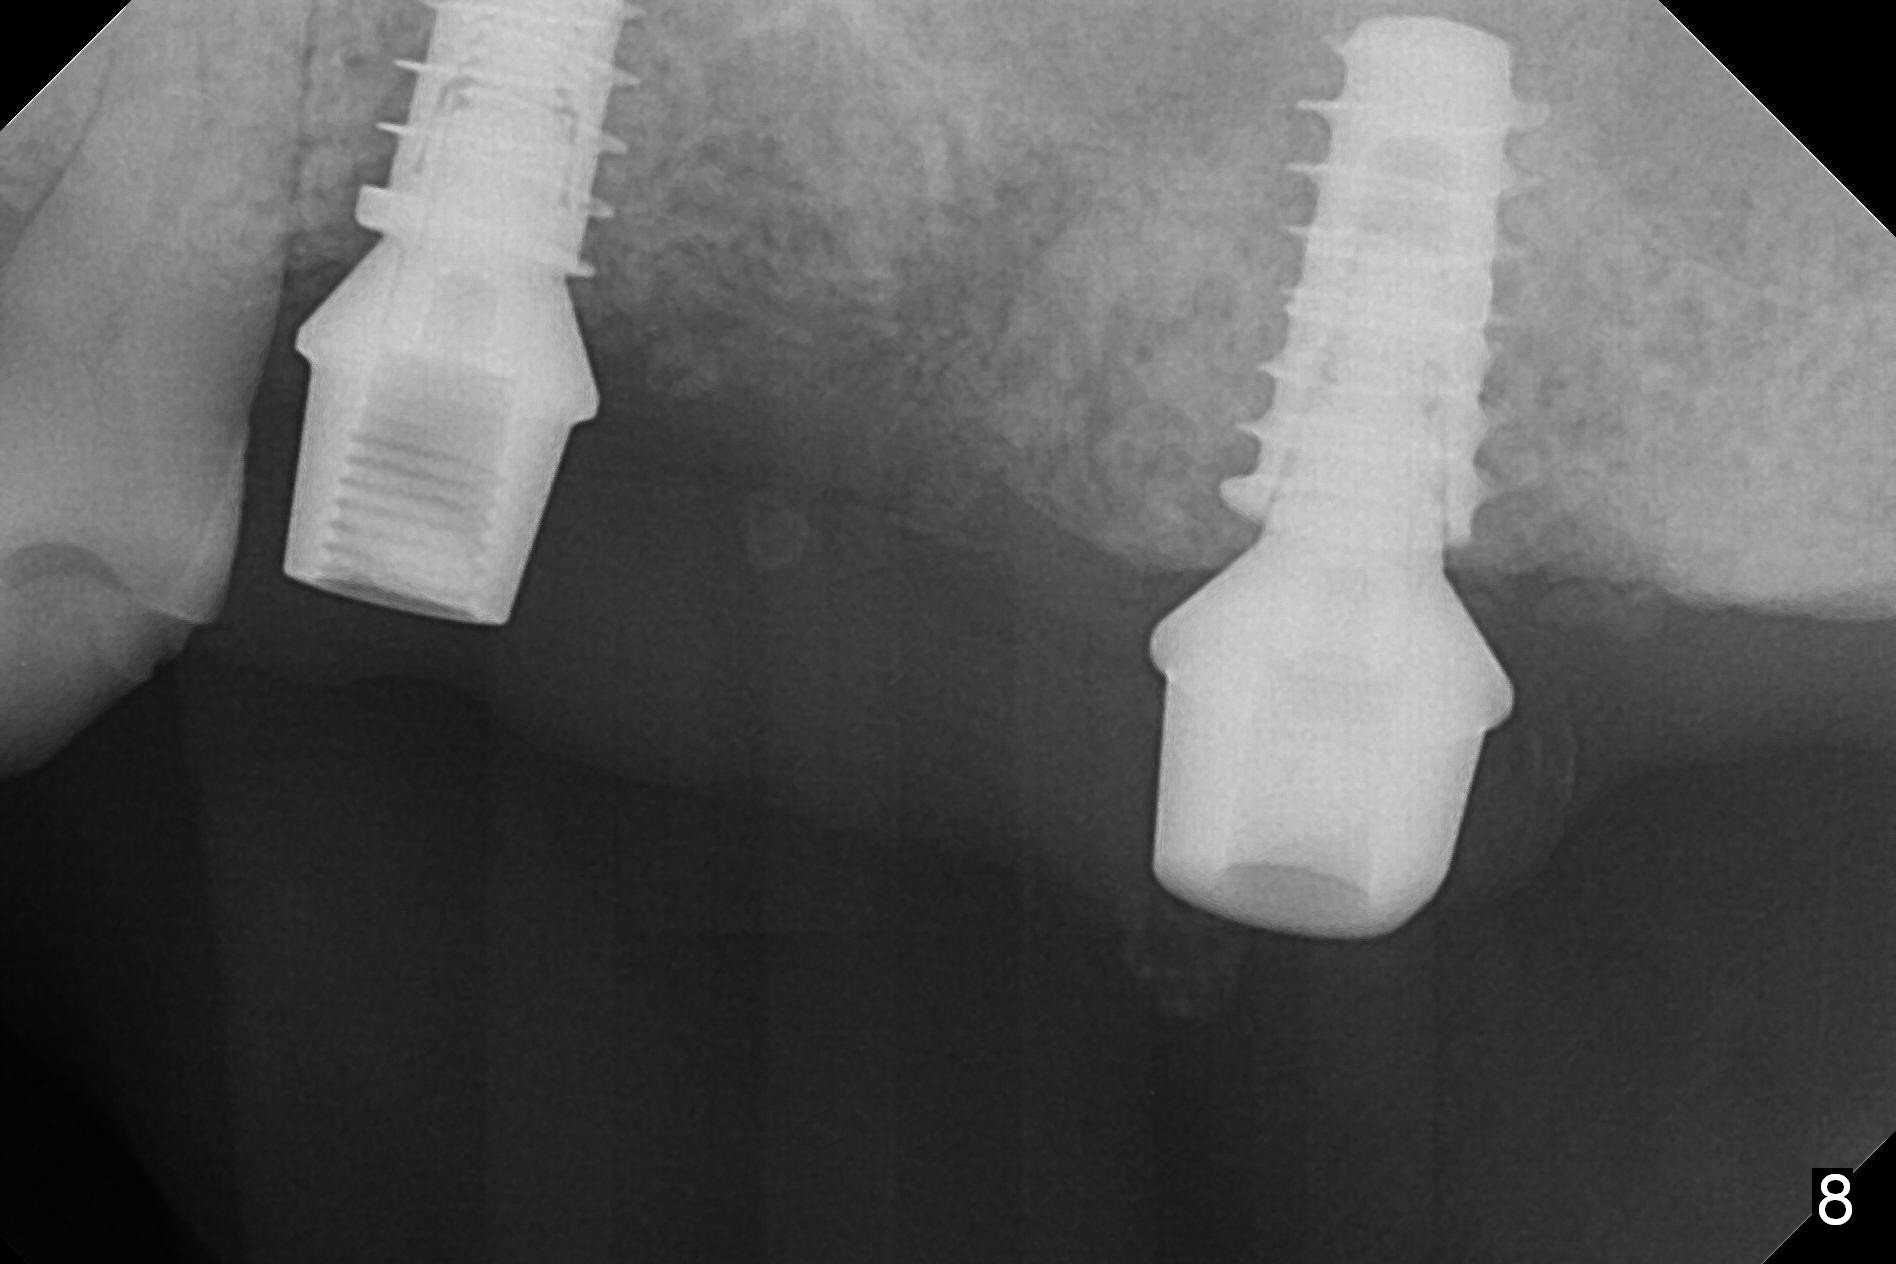

The fistula buccal to #14 remains 1 week postop (Fig.7) and disappears 1 months postop. The fistula does not re-appears 3 months postop with the implants at #13,15 apparently osteointegrated (Fig.8). With relining #13-15 provisional with increased vertical height (Fig.11), the patient has bilateral posterior contact (Fig.9), while the lower incisors do not contact the cinguli of the upper incisors (Fig.10 *). The space between the tooth #12 and the pontic #21 is unfavorable for posterior occlusal stability (Fig.11 *). Porcelain is chipped off the buccal surface of the pontic (Fig.12 *). If the patient does not afford an implant at #21 with redo crowns at #20 and 22 (Fig.13), what else could be done? He will return for #15 implant placement 4 months post socket preservation.